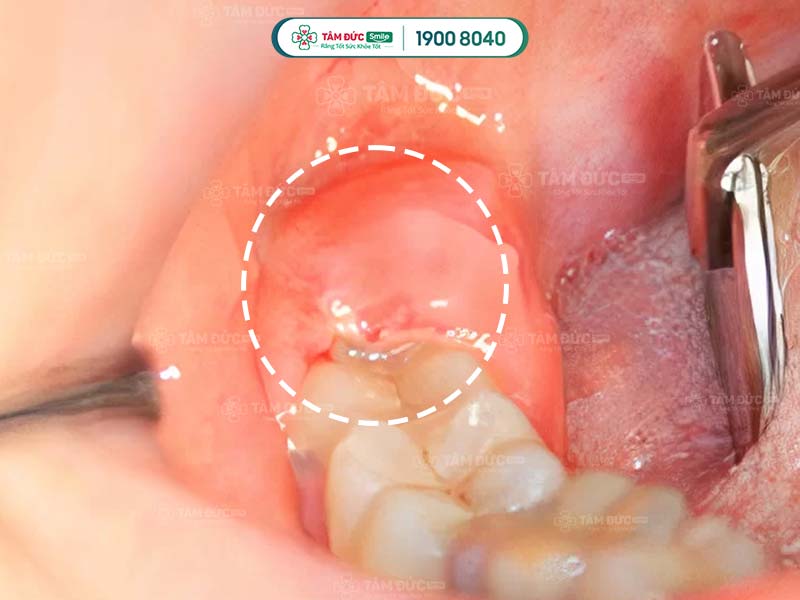

1.4. Khô ổ răng nên nhổ răng khôn 2 tuần vẫn đau

Khô ổ răng còn được biết đến là tình trạng viêm xương ổ răng, thường xảy ra sau khi nhổ răng khôn. Xác suất bị khô ổ răng chỉ chiếm chưa tới 2% trong số các biến chứng sau khi nhổ răng thường. Với nhổ răng khôn, tỷ lệ xuất hiện của biến chứng này có thể lên tới 20%.

Nguyên nhân gây khô ổ răng là do Quý khách không vệ sinh, chăm sóc răng miệng đúng cách. Điều này đã tạo điều kiện để vi khuẩn, hóa chất xâm nhập vào bên trong gây khô ổ răng. Quý khách có thể gặp phải tình trạng đau nhức kéo dài, cơn đau lan tỏa ra xung quanh, kèm theo đó là chứng hôi miệng.